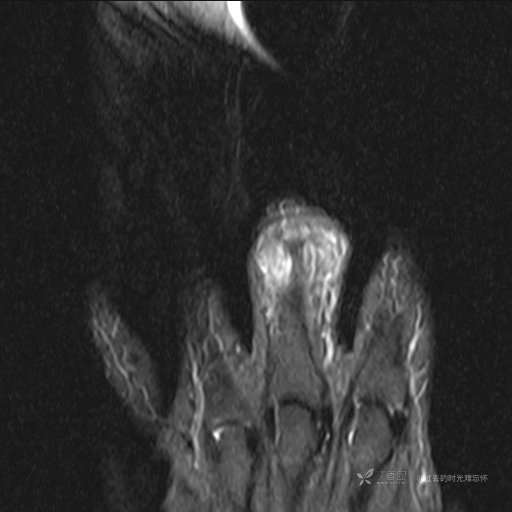

患者性别:女

患者年龄:59岁

主诉: 手指肿胀2年,其间明显肿胀,抗炎后肿胀减轻,近几日肿胀疼痛加重。

T2及T2压脂

提示:小指是伪影。